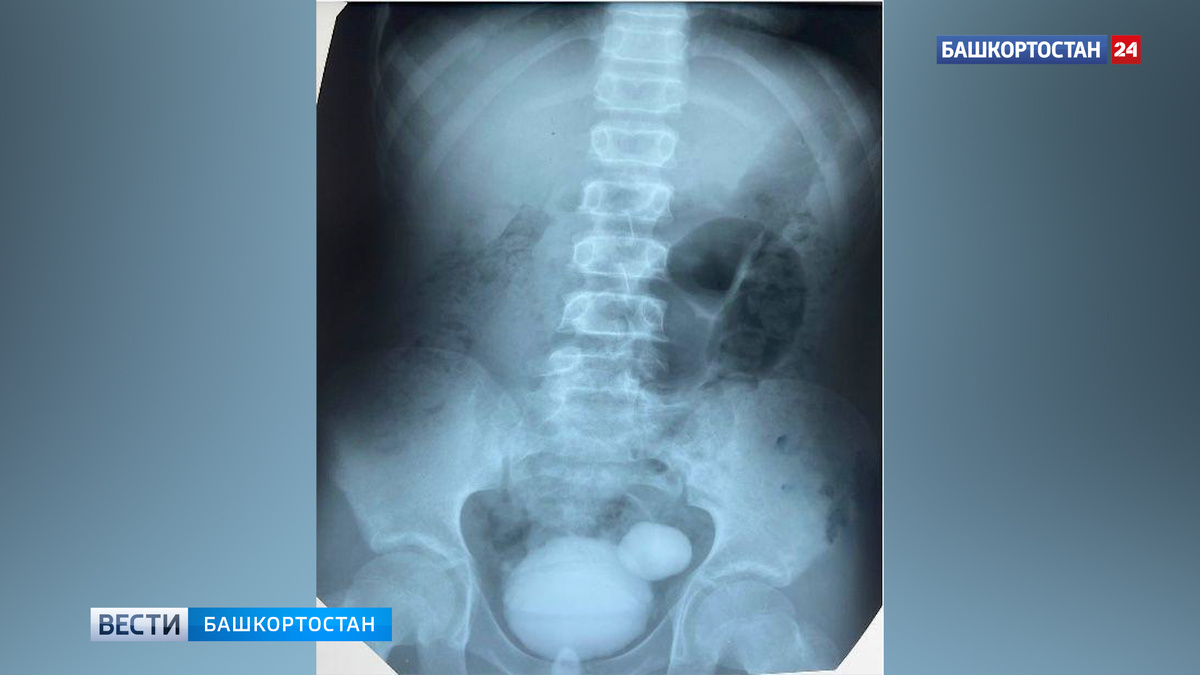

Врачи детской больницы №17 Уфы помогли 11-летнему юноше с проблемами мочеиспускания. Как рассказали в Минздраве Башкирии, у молодого пациента наблюдалось затрудненное мочеиспускание с ощущением неполного опорожнения мочевого пузыря. После проведения необходимых исследований был выявлен дивертикул размером 23х13х15 мм. Дивертикул – это мешковидное выпячивание стенки мочевого пузыря.

«Врачи-урологи провели малоинвазивную операцию и удалили патологическое образование с ушиванием стенки мочевого пузыря. Важно отметить, что данное заболевание часто не проявляется специфическими симптомами, и болевой синдром может быть слабо выражен или отсутствовать, — добавили специалисты. — Самым опасным осложнением является разрыв стенки дивертикула, что может привести к серьезным последствиям. В данном случае, благодаря своевременной оперативной помощи и профессионализму врачей, операция прошла успешно, и пациент сейчас чувствует себя хорошо, его состояние стабильно».